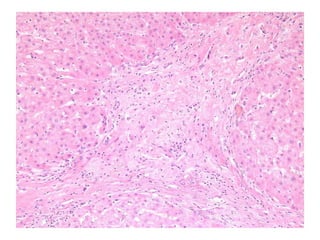

LS08-10290 Abnormal LFT, negative for Hepatitis A, B, C.  Sono: heterogeneous liver.

BS09-10453:  Dx: Chronic hepatitis, with severe activity (focal parenchymal collapse) and cirrhosis, suggestive of autoimmune hepatitis. Corresponds to: Modified Ishak stage 4/4 Metavir F4

LS08-10290 Abnormal LFT,negative for Hepatitis A, B, C. Sono: heterogeneous liver.

BS09-10453: Dx:Chronic hepatitis, with severe activity (focal parenchymal collapse) and cirrhosis, suggestive of autoimmune hepatitis. Corresponds to: Modified Ishak stage 4/4 Metavir F4